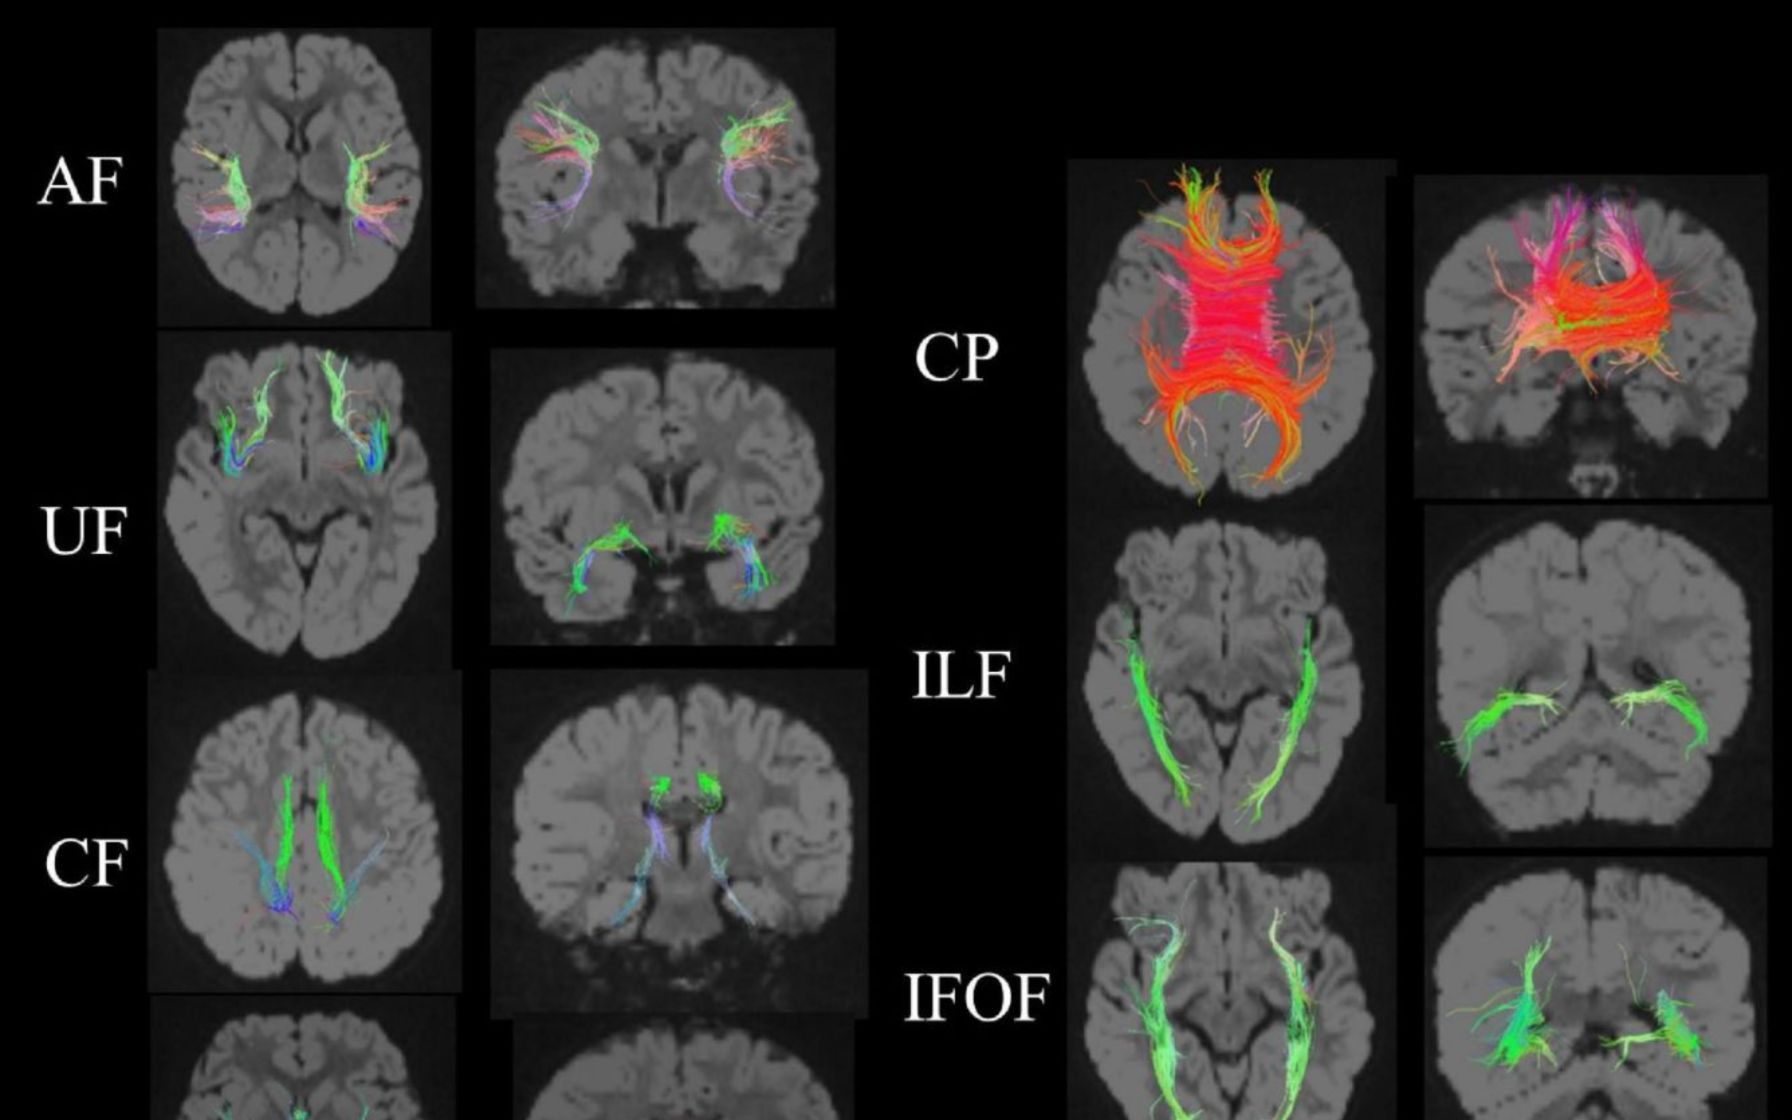

Brain Neurons Transmission